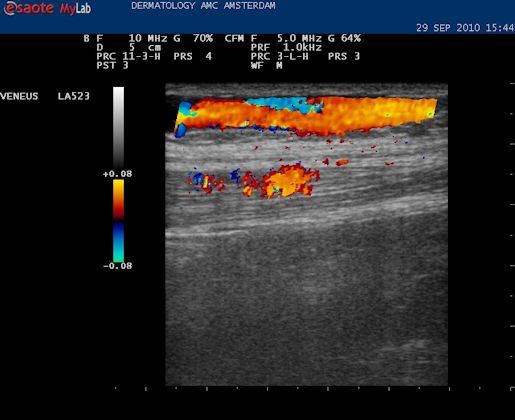

| De volgende stap is om de VSM te vervolgen naar de oorsprong in de lies, daar waar de VSM ontspringt uit de vena femoralis superficialis. Hiervoor proberen we de Mickey Mouse figuur in beeld te krijgen die hier boven te zien is. Vaak verschijnt dat al als de echokop in de liesplooi wordt gezet. Met de markering op de kop naar boven lateraal. Dan is het vat in het midden de vena femoralis. Het linker oortje, kleinere diameter, is de arterie, en het rechter oortje is de vena saphena magna. |

| Anatomie liesplooi. Lichtblauw: vena femoralis, diep systeem. Donkerblauw: vena saphena magna, oppervlakkig systeem. Rood: arteria femoralis. In de liesplooi precies waar de VSM aftakt vormen deze drie vaten de Mickey Mouse figuur. Als de echoknop markering naar lateraal staat is het rechteroortje altijd de VSM. |